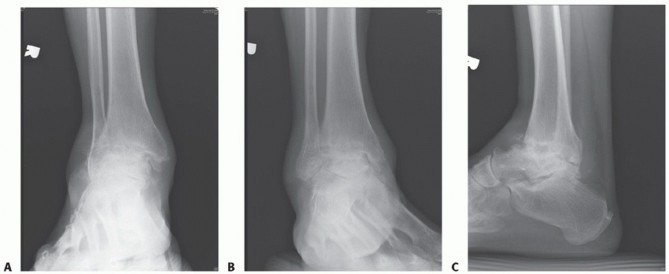

The patient was a 58-year-old man with posttraumatic talar avascular necrosis who failed brace wear.

Preoperative radiographs are shown in TECH FIG 7A-C. The patient had pain from tibiotalar arthritis due to talar dome collapse. With increasing talar collapse, the foot gradually migrated anterior to the tibia, a biomechanically unfavorable position.

Postoperative radiographs are shown in TECH FIG 7D,E. Tibiotalocalcaneal arthrodesis with a medullary nail was performed. The anatomic relationship of the foot to the tibia has been reestablished. The nail is not proud on the plantar foot. Despite the relatively large diameter of the nail, a supplemental cannulated screw can be placed adjacent to the nail from the calcaneus to the anterior tibia to provide further support to the construct. Also, a large buttress (much like the flying buttress on a French cathedral) was placed on the posterior tibia and dorsal calcaneus to increase the surface area for fusion.

- TECH FIG 7 • A-C. Preoperative weight-bearing ankle radiographs with avascular necrosis of the talar dome and some degree of anterior translation of the talus relative to the tibial axis. A. AP view. B. Mortise view. C. Lateral view. D,E. Postoperative weightbearing ankle radiographs of the same patient after tibiotalocalcaneal arthrodesis. Fusion appears to have been successful based on the bridging trabeculation at the arthrodesis sites. In our experience, the increased surface area afforded by the bone graft to the prepared posterior tibia and dorsal calcaneus increases the chance of fusion. Note that the physiologic relationship of talus to tibial shaft axis has been reestablished. Despite the nail's relatively large diameter, a supplemental cannulated screw could be passed adjacent to the nail to provide greater stability to the construct. D. AP view. E. Lateral view. PEARLS AND PITFALLS